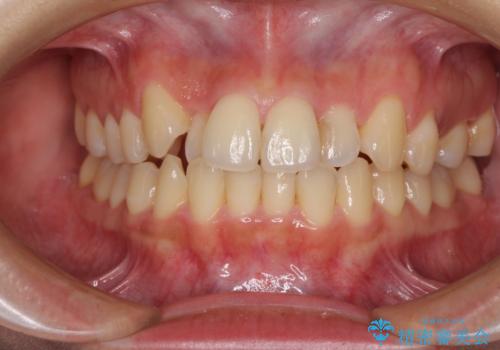

- 前歯のデコボコを気にして来院された患者様です。

上顎右側犬歯が八重歯になっており、それによって奥歯が前方に移動しているため、右側の咬み合わせの改善が必要と判断されました。